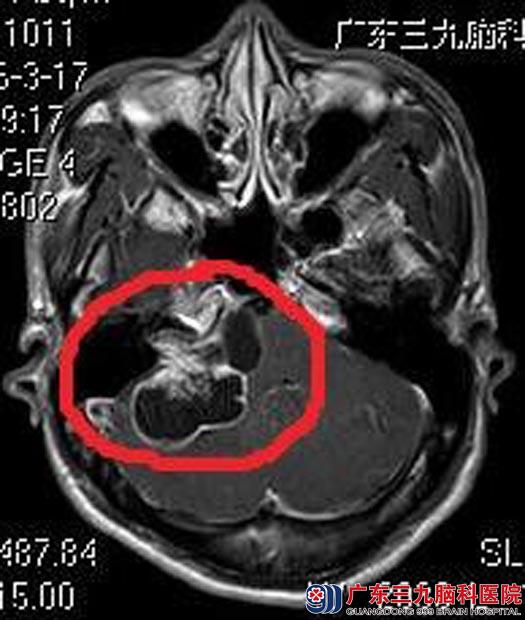

刘先生4个月前出现右耳吹风样响,休息后无明显好转,伴有听力下降,呈进行性加重,以为是工作精神压力大,在心理科就诊,头颅CT检查时发现:右侧桥小脑角占位性病变。

进一步MR检查提示:右侧桥小脑角区示一大小约54.9mm×37.1mm×30.3mm,囊实性占位性病变,以囊性为主,考虑听神经鞘瘤。

▲术前